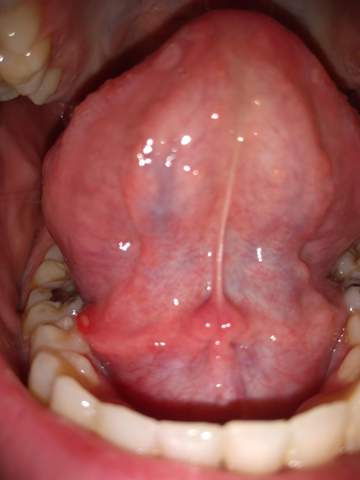

Und Immer Wieder Das Zungenbandchen Szet Konzept